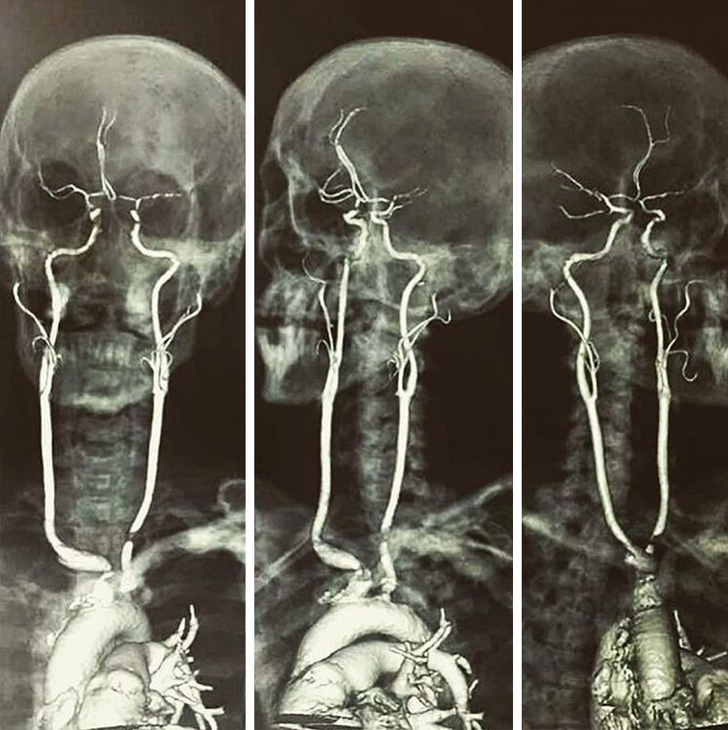

Así se ven las arterias carótidas